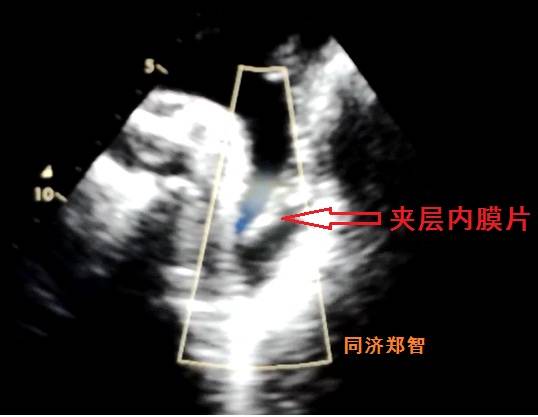

病例八

有时在彩超中也可以观察到内膜片,但其准确性不高,存在假阴性和假阳性的可能。